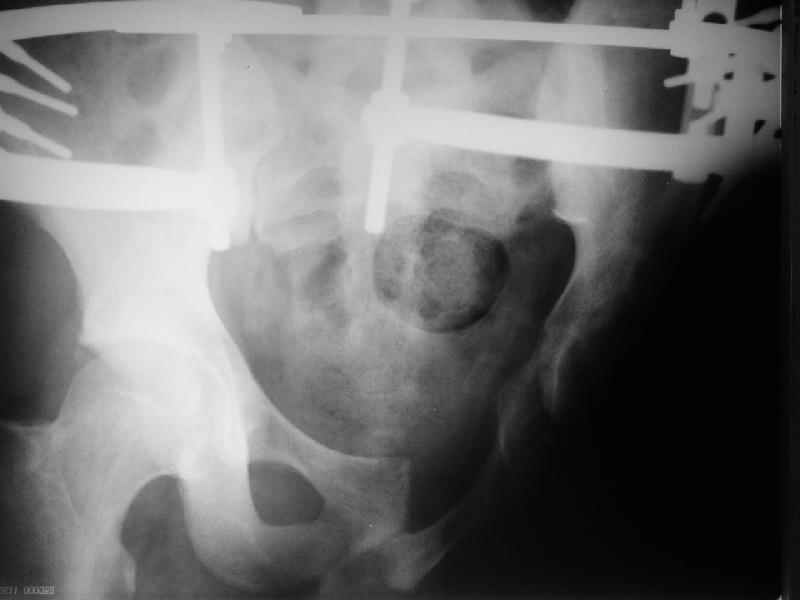

Уважаемые коллеги, в нашу клинику поступил молодой человек (25 лет),получивший травму в октябре 2003. До настоящего времени находился на лечении в другом лечебном учреждении, где пластически закрывали дефект (наша бригада на выезде накладывала аппарат). Сейчас аппарат демонтирован, можно было бы заняться протезированием, но после консультации протезиста из нашего ортопедического предприятия, оказалось, что сделать протез в данном случае не представляется возможным, поскольку нет опыта протезирования при отсутствии седалищной кости и опорной кожи (предлагается малофункциональная конструкция годов 60-х). Подскажите, как можно помочь пациенту, у нас или за рубежом. Травма производственная, с оплатой проблем быть не должно.

Уважаемый доктор Салаватов! Мы получили информацию о пациенте с отрывом левой нижней конечности и повреждениями области таза.

Отсутствие седалищной кости и грубые рубцовые деформации кожных покровов делает так называемую культю неопороспособной. Больному необходимо провести подготовку к протезированию комплексного характера, включая возможные хирургические вмешательства, например, проведение кожной пластики по уменьшению рубцового дефекта по методу